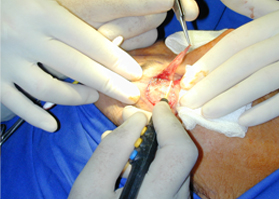

經典案例